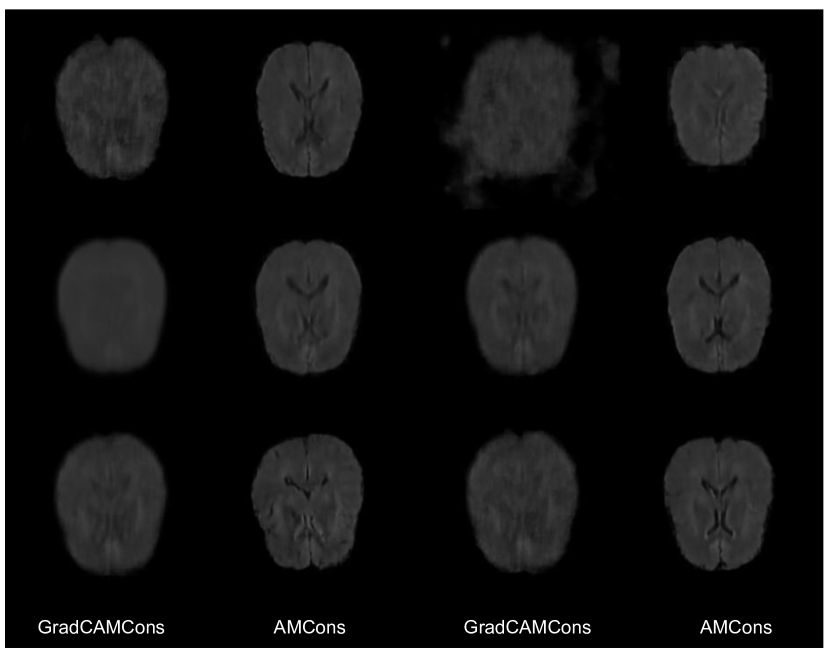

3.4 On the role of gradients in VAEs

Even though there exist a few initial attempts to integrate attention maps on the task of unsupervised anomaly detection, how gradient-based attention behave on anomalous patterns remains unclear. For instance, [29] argue that anomalies produce larger gradients in the learned latent representation, which results in higher activated attention maps. On the other hand, [47] states that the VAE only focus on normal patterns (with which it has been trained), thus anomalous regions produce smaller absolute value gradients. These inconsistencies in the literature have motivated us to analyze the underlying role of the gradients in the context of brain images analysis. Thus, we performed several experiments to analyze the behaviour of grad-CAMs in anomaly localization compared to non-weighted activation maps (AMs), which are computed as:

| (6) |

In particular, we could not find any benefit on gradients weighting other than serving as a scaling factor for attention maps to fall on non-saturated range of values of typically used activation functions, such as the sigmoid operation in Eq. 2 (see Figure 2, where we show that the values obtained by both types of attention are highly correlated). Furthermore, we found that the reconstructed images derived from the gradient-based attention contained more errors compared to those reconstructed with attention on the activation maps (Eq 6). We refer the reader to Section 1 of Supplemental Material for the detailed results concerning the role of the gradients.

In this section, we describe the empirical analysis on the gradients role in attention-based anomaly detection using VAEs. To this end, a VAE is trained on normal brain MRI images, and attention maps are extracted for anomalous images. Concretely, we extract Grad-CAMs as defined in Eq.2, and non-weighted activation maps (AMs) as following Eq. 6. A representative case is shown in Figure 2 of the main manuscript. Under the explored setting, VAEs Grad-CAMs produce similar attention maps compared to so solely AMs. In particular, we could not find any benefit on gradients weighting other than serving as an scaling factor for attention maps to fall on non-saturated range of values of typically used activation functions, such as sigmoid operation in Eq.2. Although Grad-CAMs have been widely used in discriminative models to discern regions of interest in the image using class-specific gradients, its usefulness in generative models such as VAEs seems to be limited. In this case, the information encoded in the VAE seems closely related to the patterns detected by the convolutional filters in their early layers, without discarding any task-specific information.